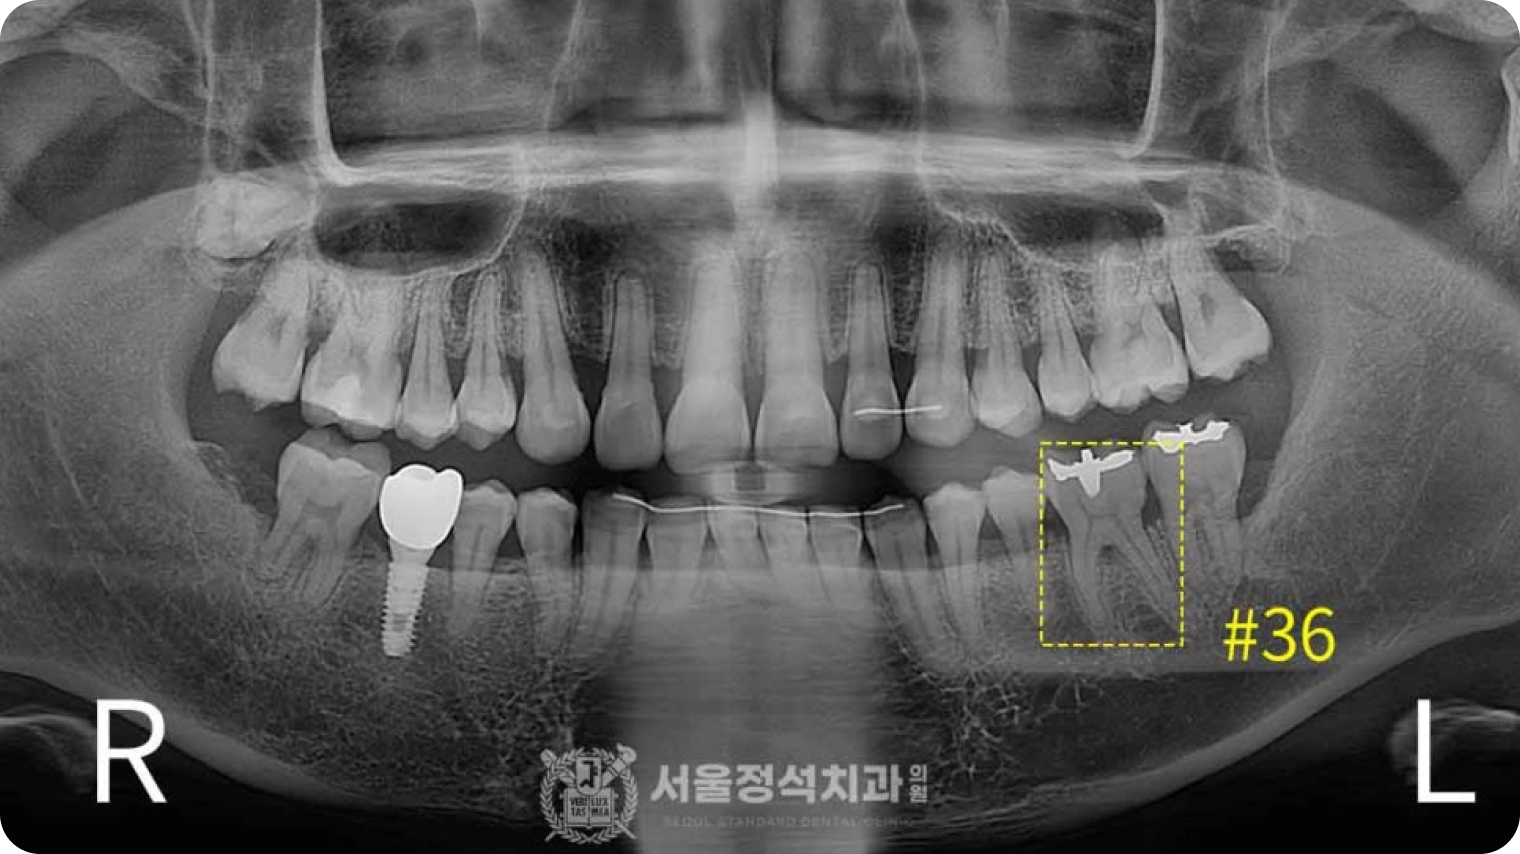

신경치료

신경치료

신경치료

충치나 다른 원인으로 인해 치아 속까지 염증이 생긴 경우 손상된 치아 내부 신경 조직을 제거하고 치과용 충전재료로 채워 기능과 형태를 보존시키는 술식입니다.

보철치료

보철치료

보철치료

치아의 일부 상실된 부분을 정상적인 모양으로 회복시켜주며 인레이, 크라운, 브릿지 등 보철 수복을 통해 자연치아를 보호하고 재건을 돕습니다.